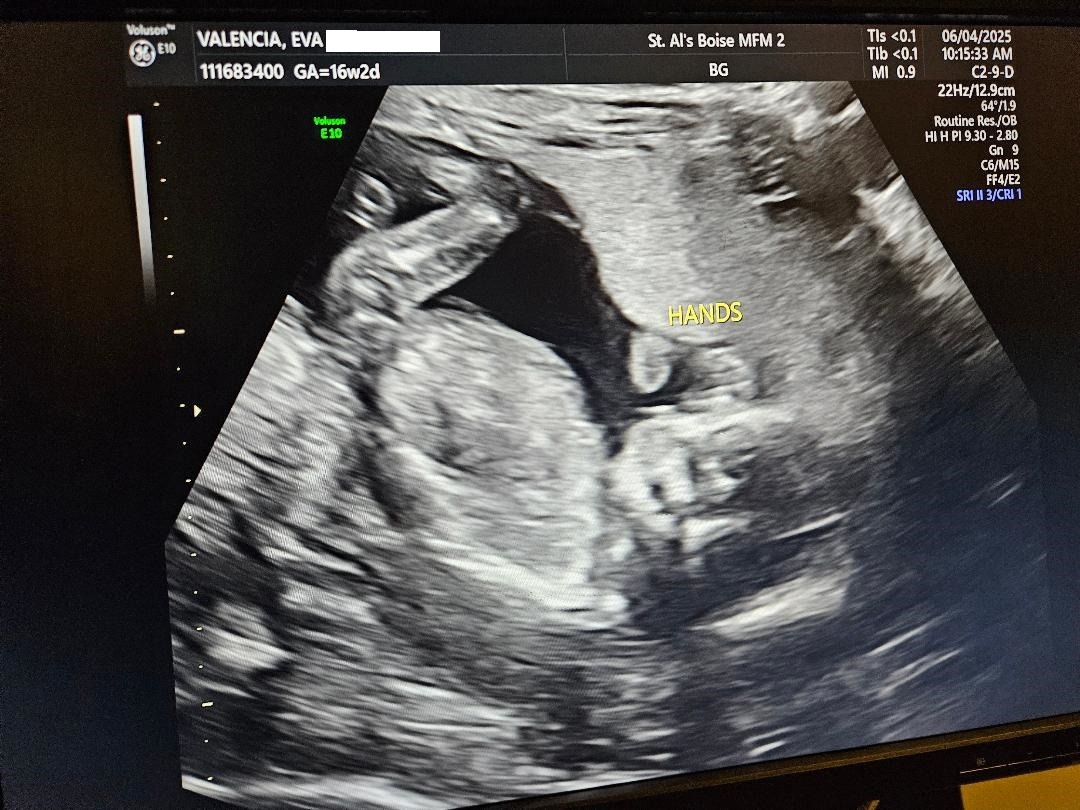

My Wife Eva and I are expecting our 5th child. We were given some devastating news. Eva was diagnosed with something called "placenta accreta" along with a "previa placenta". Eva’s cervix is also smaller than usual.

Eva was seen by two fetal medicine doctors here and it has been recommended that we fly to The University of Utah Hospital’s MFM (Maternal Fetal Medicine) clinic in Salt Lake City. We will be doing this on Tuesday June 10th with an appointment on Wednesday June 11th with the premier doctor in all of the United States of America for these specific types of conditions. Per the Boise Idaho doctor’s, it was advised that we stay and live in Utah, close to the clinic for the duration of the pregnancy. The thinking behind all of this is both to keep Eva and the baby close to the Hospital in the event of an emergency, so both of them can be attended to quickly by the best doctors and surgeons in the country for this situation. The hope though is that Eva can make it to 32 weeks and have the baby at that time. We have been informed that the baby, regardless of birth time, will spend a good amount of time in the NICU. If Eva has an emergency then both she and the baby will be there much longer. In this scenario we were told months, not weeks, of a hospital stay for both the baby and Eva. Of course we are praying for her and the baby to make it to 32 weeks so both of them come out of this together, healthy. Eva is currently 16 weeks.